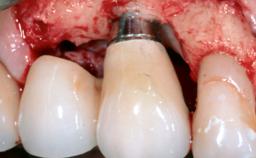

Resective Surgical Treatment of Peri-Implantitis Including Implantoplasty

In this case, Myroslav Solonko, Ignacio Sanz Sánchez and Mariano Sanz present a treatment that aims to eliminate exposed implant threads by modifying the implant surface, converting a moderately-rough surface into a smooth surface.